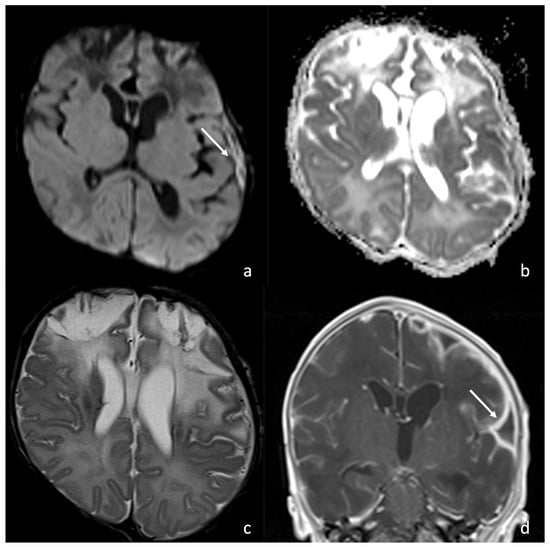

6.2. Infarcts